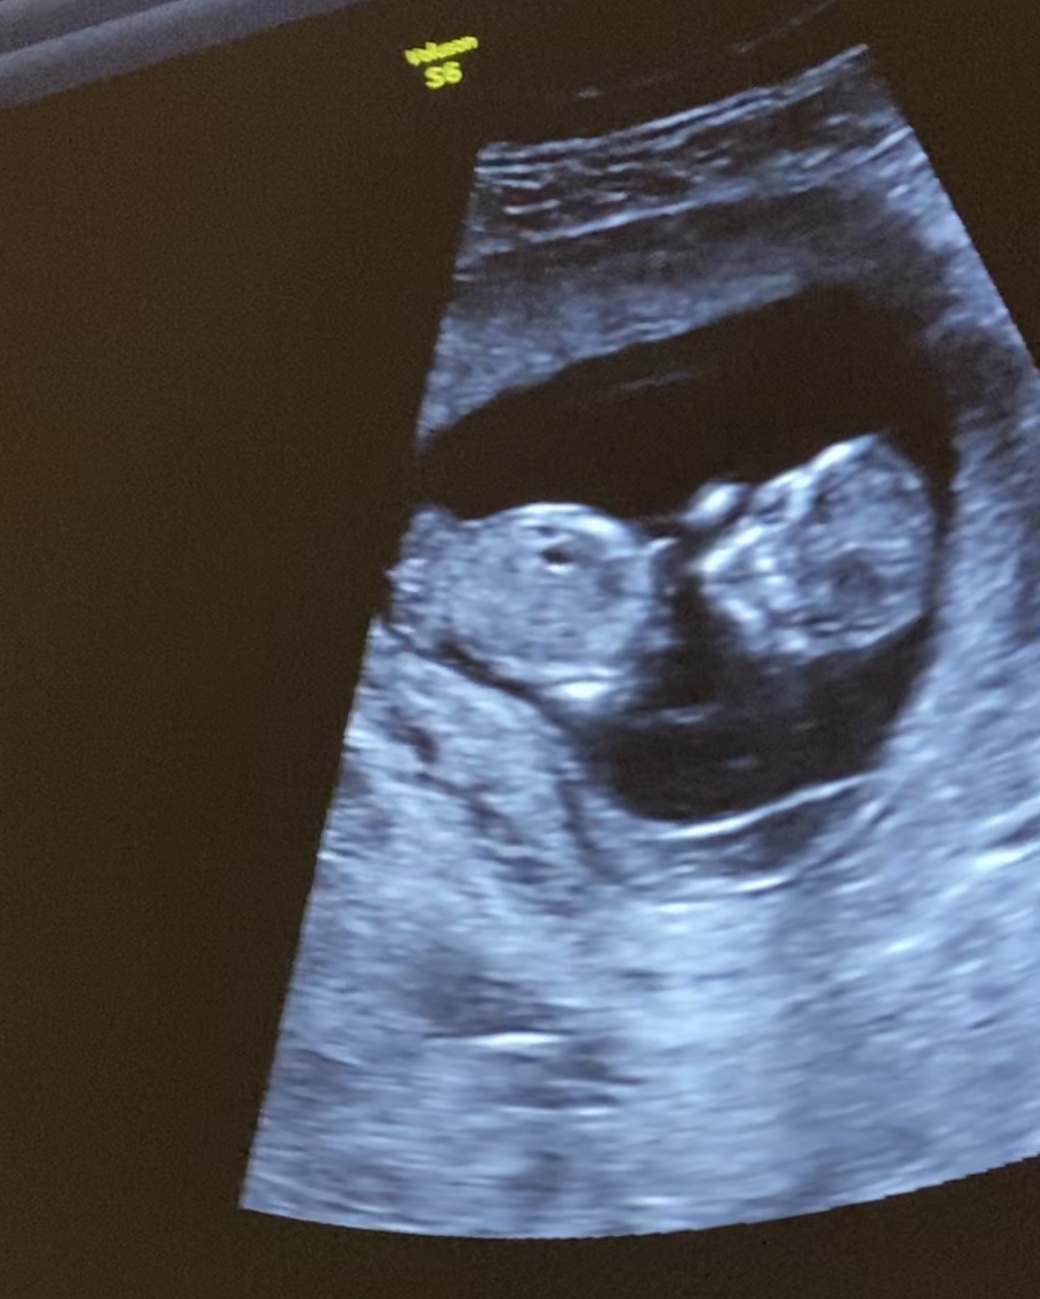

I just had my ultrasound and I am 12+1. I know it痴 face on, and I know it痴 too early to know for sure, but I知 wondering if these are the three lines I always hear about, or if it might be testicles next to a penis.

The top pic is not suitable for guessing. That's not the three lines, you can't tell gender from a frontal shot like that unfortunately.